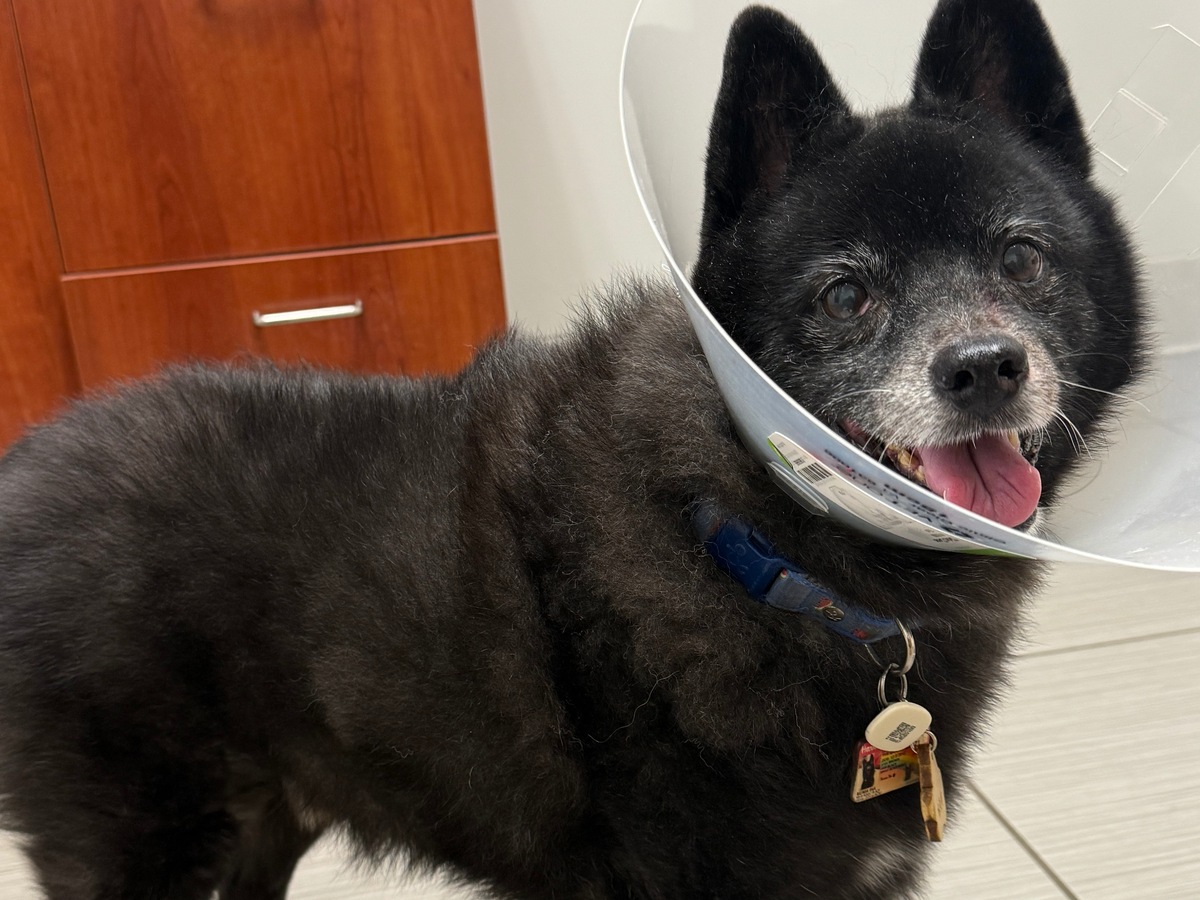

Hi, my name is Caitlyn and this is my world, Kuma. Kuma was having sneezing fits and a runny nose only from the left nostril. I thought he was having allergies. As time went on, he sneezed and I saw a big green booger hanging out of his nose. I called my vet to set up an appointment to see if we could get this infection to go away. The vet gave him antibiotics to help with the infection. As weeks passed, he had clear boogers and it looked like the infection went away. I took him back for a follow-up to see why his sneezing fits still did not stop. The vet sent us home with more antibiotics, seeing if a prolonged length of antibiotics would help. Another week went by and still no improvement. The vet called and wanted to schedule an X-ray to see if there was anything in his nose and sent him home with more antibiotics. Kuma went in for his X-ray and I got the call with the findings... I knew when I answered the phone and he started talking, it wasn't good. They found a mass located in his left nasal cavity. He said that they are unsure if it is a cancer lump due to his age. Hearing about him possibly having cancer made my heart drop. Knowing that I want to start right away just in case this takes him away from me. I asked them what the next steps were moving forward. They recommended that we start with a CT to get a better look at what it is and then a rhinoscopy to see it. Unfortunately, they are unable to do the procedure in-house and had to refer us to other vet hospitals. VCA called 2 days later giving an estimate of 8K for the procedure.

Kuma finished his CT scan and it is confirmed that he had a tumor located in his left nasal cavity. The tumor is over 4cm long slowly moving back towards his brain and down his throat. They are going to blind biopsy the tumor to run some test.

Kumas Dr at VCA sent over the CT scans of Kumas skull. he has a follow up appointment in a month to see how much the tumor has grown. I am currently trying to stop it from getting bigger. Trying all these things that I have been recommended before chemotherapy. He will have another CT scan in one month to see how the tumor is doing.

This is only the start of his journey and I wanted to start right away cause I'm not ready for him to leave me.

Kuma, my beloved fur-son, needs your help to get the necessary medical treatment. Any support you can provide would be greatly appreciated.